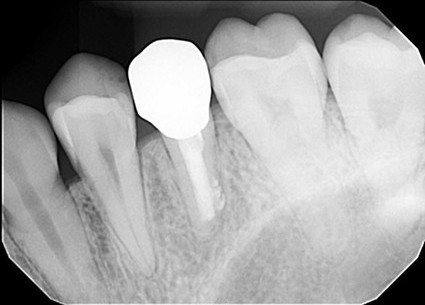

| 主訴 | 膿で腫れて痛みが強い、他の歯医者で抜歯しかないと言われ相談で来院 |

| 状態 | 自発痛もかなり強く、写真のように膿が溜まって腫れ上がっている状態 |

| 治療内容 | X写真から根先部の根先病変が原因と思われるため、根管治療を行った。 骨成長因子を用いて、骨の再生を促した。 結果、2年経過後病変の大きさが1/3まで縮小し、骨の再生が認められる。 本人も症状や違和感がなくなったため、一時的に補綴物をセラミックで行った。 |

| 料金 | 根管治療10万円、ファイバーコア2万円、EーMAX11.5万円 |